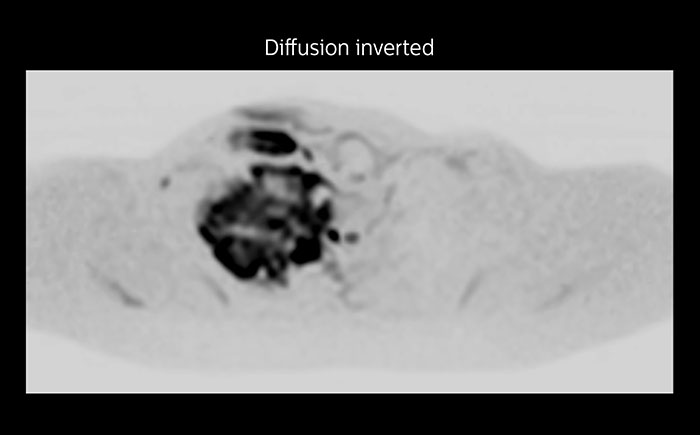

Whole body diffusion

A 61-year-old female with a malignant lymphoma underwent an MRI exam with whole body diffusion weighted imaging (DWIBS) as well as PET. On the images shown, the resolution of DWIBS is better than PET, which allows visualization of the small pelvic lesions and almost no distortion is seen in the neck area.